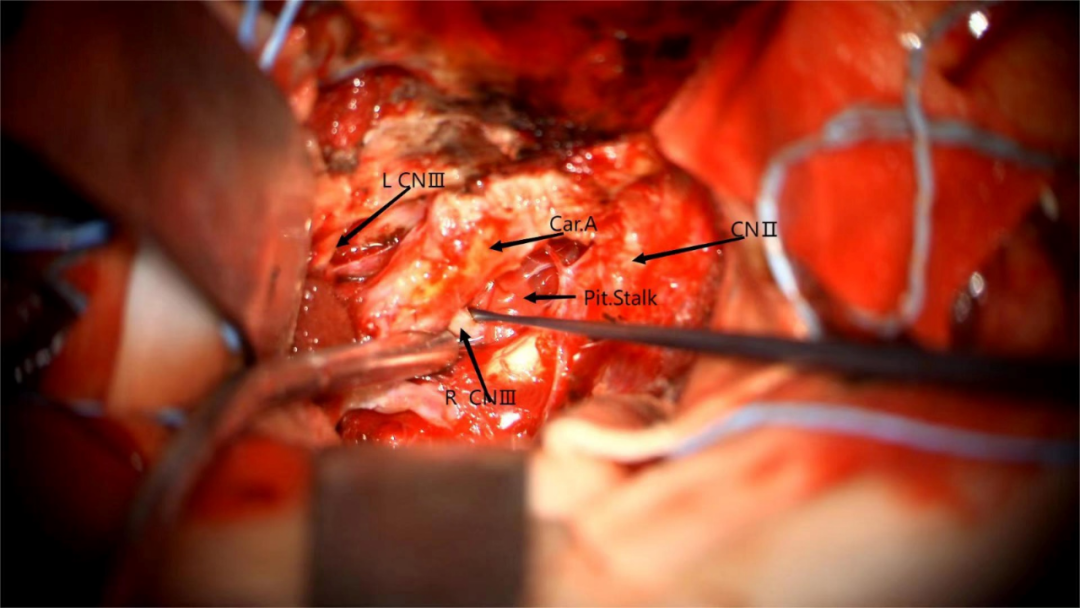

术中图片:

图21. 硬膜外入路,暴露前床突

图22. 磨除前床突

图23. 打开硬脑膜,抬起额叶,暴露肿瘤,处理肿瘤基底

图24. 分离肿瘤与颈内动脉黏连

图25. 分离肿瘤与视神经黏连

图26. 分块切除肿瘤

图27. 分离肿瘤与动眼神经黏连

图28. 分离肿瘤与大脑前动脉黏连

术后患者意识清楚,四肢活动好,对答切题,左眼视力较术前相仿,左侧动眼神经轻度麻痹,进一步康复治疗中。